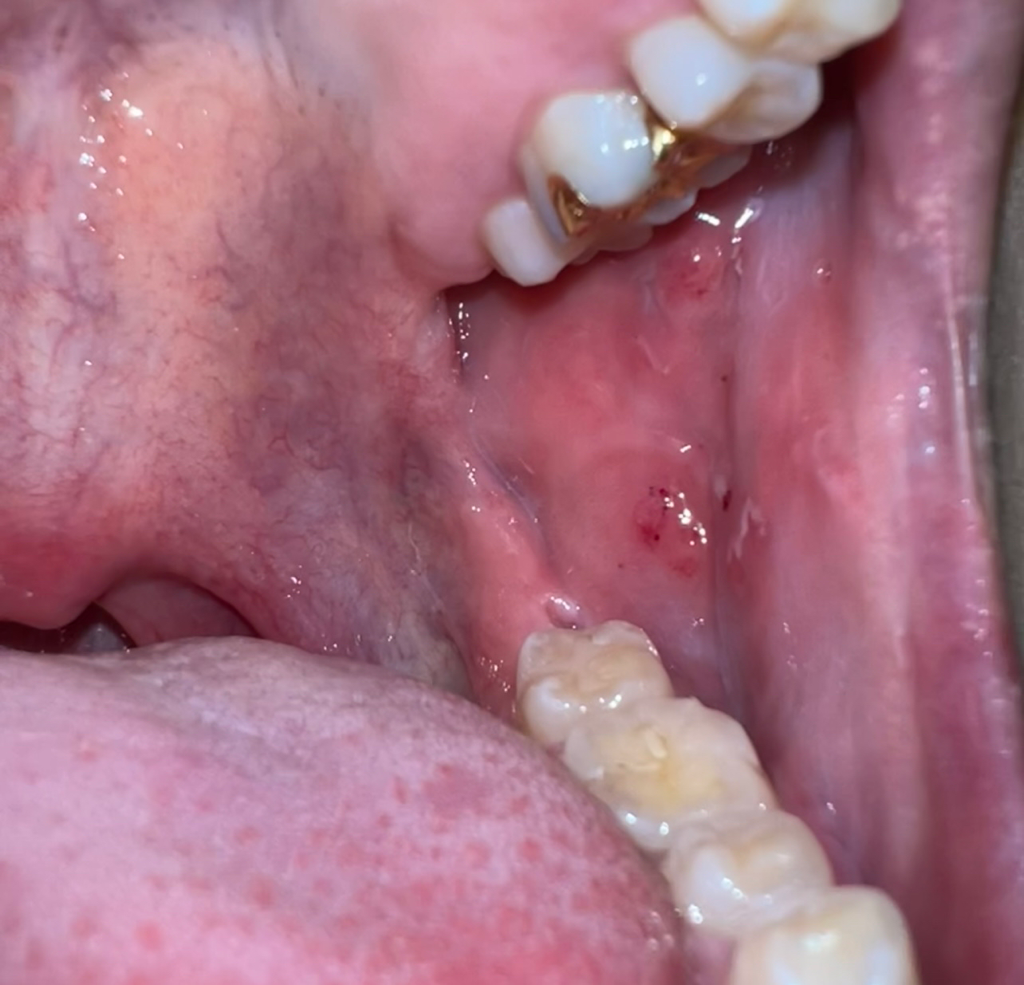

입안에 하얀게 자꾸 오랫동안 생깁니다 제발 살려주세요 구강암 후두암

6주전 제가 관계 가졌던 사람이 hpv 고위험군 68 51 저위험군 43이 나왔습니다

제가 손으로 먼저 해줬고 그 손을 빨게 한뒤 저랑 키스 구강성교 항문애무를 받았습니다

저는 지금 입안에 입병들이 많이 났고 목이 아픈데 이거 위험한 거 맞죠?? 구강암,후두암 너무 걱정됩니다 ㅠㅠ

• 1번 째 사진

아마 볼살이 치아에 씹혀서 상처가 생겻고 계속 그부위가 자극을 받아서 생긴 상처 같습니다. 구강암은 아니니 일단 걱정하시고 치과에 가셔서 소독을 받으시는게 좋을것같습니다.

대학병원의 구강내과에 내원하셔서 해당 부위의 조직검사를 받아보시는것이 좋겠습니다.